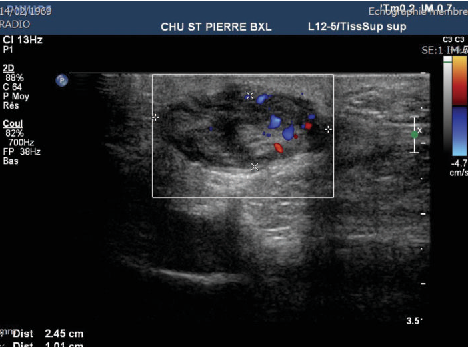

초음파 검사에서

발바닥 근막 섬유종은

저에코/동등에코의 결절이 보이고

발바닥 근막과 연결성이 확인됩니다.

도플러 검사에서

혈류 증가 소견이 동반될 수 있으며

석회화는 거의 생기지 않습니다.